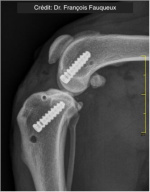

Radiologické snímky